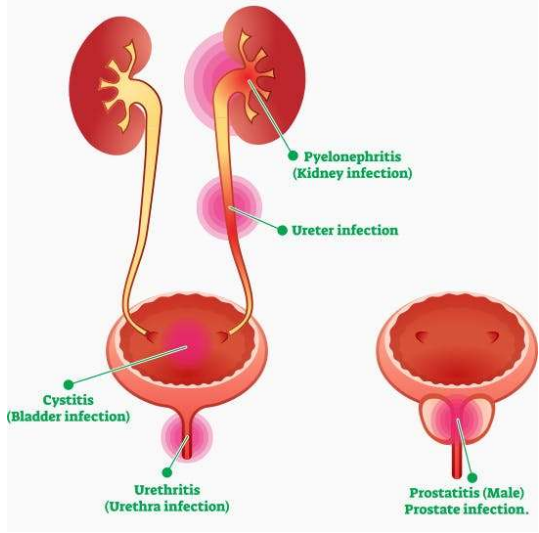

Urinary tract (비뇨기계)

Urinary tract(비뇨기계)의 구성

- Kidney (콩팥, 신장) : 소변 생성

- Ureter (요관) : 신장에서 생성된 소변을 방광으로 운반

- Bladder (방광) : 소변 저장

- Urethra (요도) : 소변을 외부로 배출하는 마지막 경로

| UPPER urinary tract infection (요관) | |

|---|---|

| Kidney infection | Pyelonephritis (신우신염) |

| Ureter infection : 단독 발생 적음 | Ureteritis (요관염) |

| LOWER urinary tract infection (요도) | |

|---|---|

| Bladder infection : 압도적으로 많음 | Cystitis (방광염) |

| Urethra infection : 단독 발생 적음 | Urethritis (요도염) |

🟡 Bacterial prostatitis (세균성 전립선염)

- 성숙한 수컷 개에서 주로 발생하며, 만성 또는 급성으로 나타남.